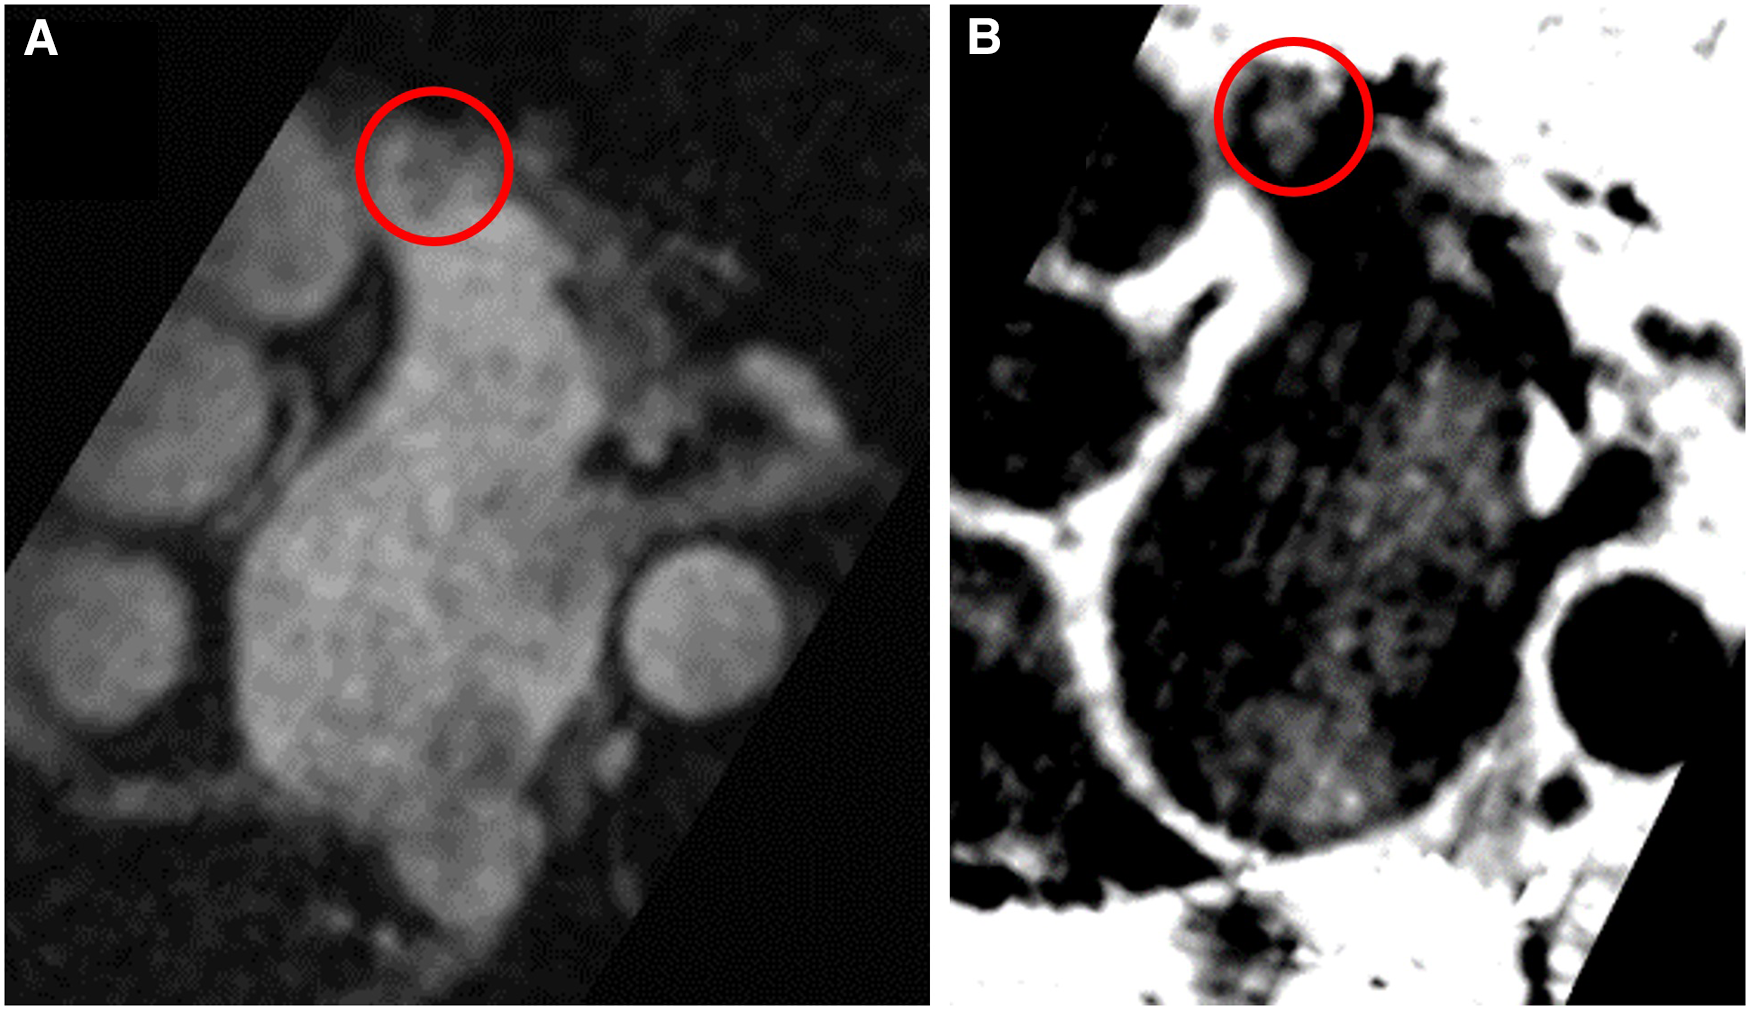

In 67 patients (94.4%), both TEE and CMR excluded the presence of LAA thrombus. In 1 patient (1.4%), both TEE and CMR showed the presence of thrombus [Figures 1, 2; a supplementary movie file shows the thrombus detected with TEE in motion (see Supplementary Video S1)].

Figure 1

Left atrial appendage thrombus circled in red on CMR T2-preparation (T2prep) BOOST sequence images. Panel (A): Magnitude image of T2prep BOOST. Panel (B): Dark-blood image of T2prep BOOST (Heart and Vascular Center, Semmelweis University).